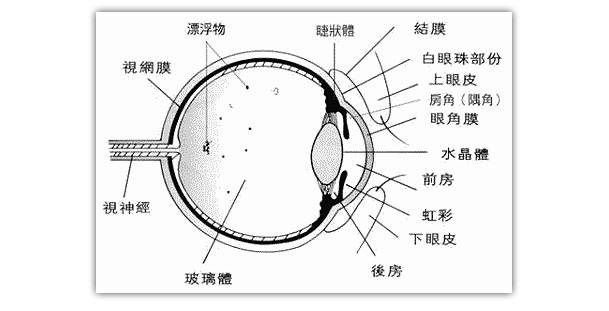

A:飛蚊症是指眼前有飄動的黑影,尤其是看白色背景的時候症狀更加明顯,同時有時候有些人會伴有閃光感,眼前一亮一亮的症狀,引起的原因主要是玻璃體液化和後脫離。絕大多數的飛蚊症都是生理性,但是有大約20%的飛蚊症,可能是病理性,具有威脅視力下降的情……

A:飛蠅症又稱飛蚊症和玻璃體混濁,是指玻璃體內出現不透明體,造成患者視物出現模糊。人出生時玻璃體呈凝膠狀態,是重要的屈光介質,正常的玻璃體隨著年齡逐漸出現液化,從而導致玻璃體混濁。此外,一切玻璃體混濁是由於病理原因所導致,例如玻璃體出血、葡萄……

A:眼前出現飛蚊的症狀往往是因為玻璃體發生了液化、變性和混濁,通常情況下玻璃體的混濁,比較多見於近視眼的人和年歲比較大的中老年人,還要特別重視的一個問題是當眼底有病變發生的時候,也會出現玻璃體的混濁、玻璃體混濁的加重,這時候眼前飛蚊的症狀需要做……

A:眼睛裡有飛蚊的現象主要是因為玻璃體發生了液化、變性和混濁,玻璃體原本在眼睛裡邊是一個膠凍狀的結構,由於近視眼以及中高度近視或者年齡過大了,中老年人就會出現玻璃體的液化、變性和混濁,這種情況下很難通過任何治療,將已經液化的玻璃體恢復到膠凍狀的……